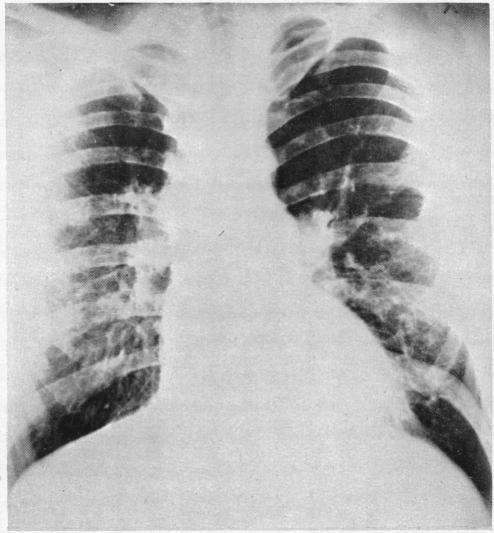

Aortic origin of the right pulmonary artery.